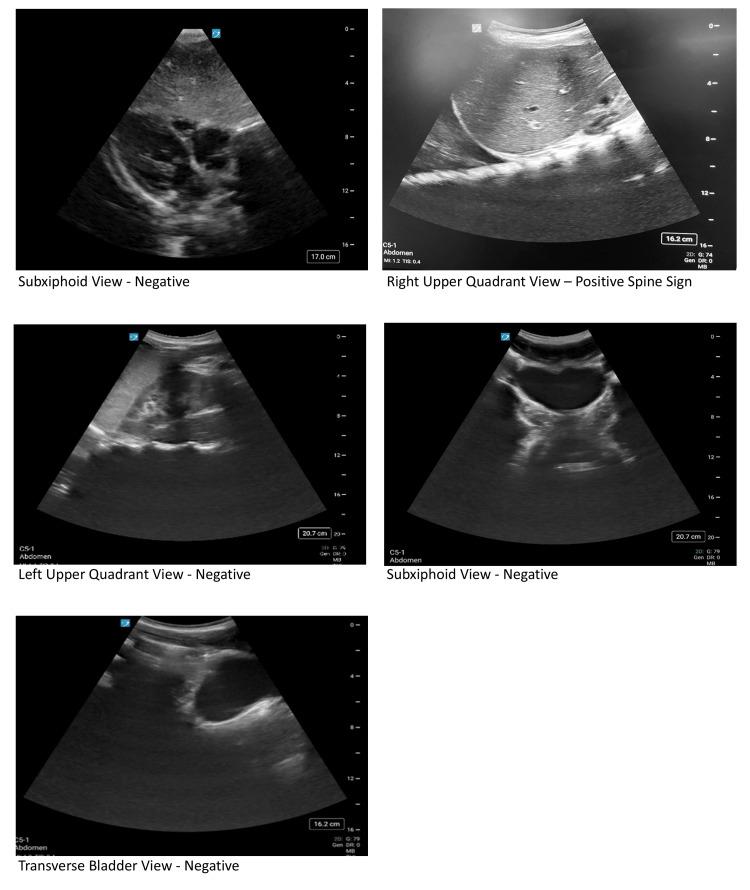

Firearms are the leading cause of pediatric death in the U.S., with a rising number of firearm-related injuries presenting to Pediatric Emergency Departments (PED). Trauma centers that manage firearm injuries have higher rates of weapon confiscation. Many healthcare workers have encountered concealed firearms in the ED, despite a lack of workplace firearm handling training. To address this gap, this technical report describes a novel simulation-based curriculum for Pediatric Emergency Medicine (PEM) trainees involving a 15-year-old male presenting with a gunshot wound (GSW) to the chest requiring chest decompression, intubation, and blood products. A concealed firearm discovered on the patient required proper handling protocols. Afterward, a debrief was conducted, and participants completed an evaluation based on pre- and post-simulation knowledge using a 5-point Likert scale (1 = Strongly Disagree, 5 = Strongly Agree). Learners rated the simulation as highly relevant (Mean (M) = 4.8) and realistic (M = 4.7) and reported improvements in teamwork and communication skills (M = 4.6). They also demonstrated increased comfort with identifying firearm injury patterns (pre M = 4.2, post M = 4.6), stabilizing critically ill trauma patients (pre M = 4.1, post M = 4.4), handling firearms in a healthcare setting (pre M = 3.4, post M = 4.3), and functioning effectively as a team in the trauma bay (pre M = 4.5, post M = 4.6). This simulation was well received and provided a psychologically safe environment for trainees to address key knowledge gaps and improve comfort with firearm-related trauma care and safety practices in the pediatric emergency department.